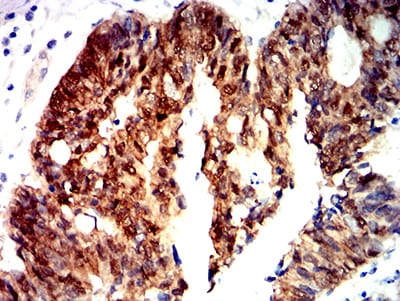

Immunohistochemical analysis of paraffin-embedded human cervical cancer tissues using CTNNB1 mouse mAb with DAB staining.

Immunohistochemical analysis of paraffin-embedded human rectum cancer tissues using CTNNB1 mouse mAb with DAB staining.